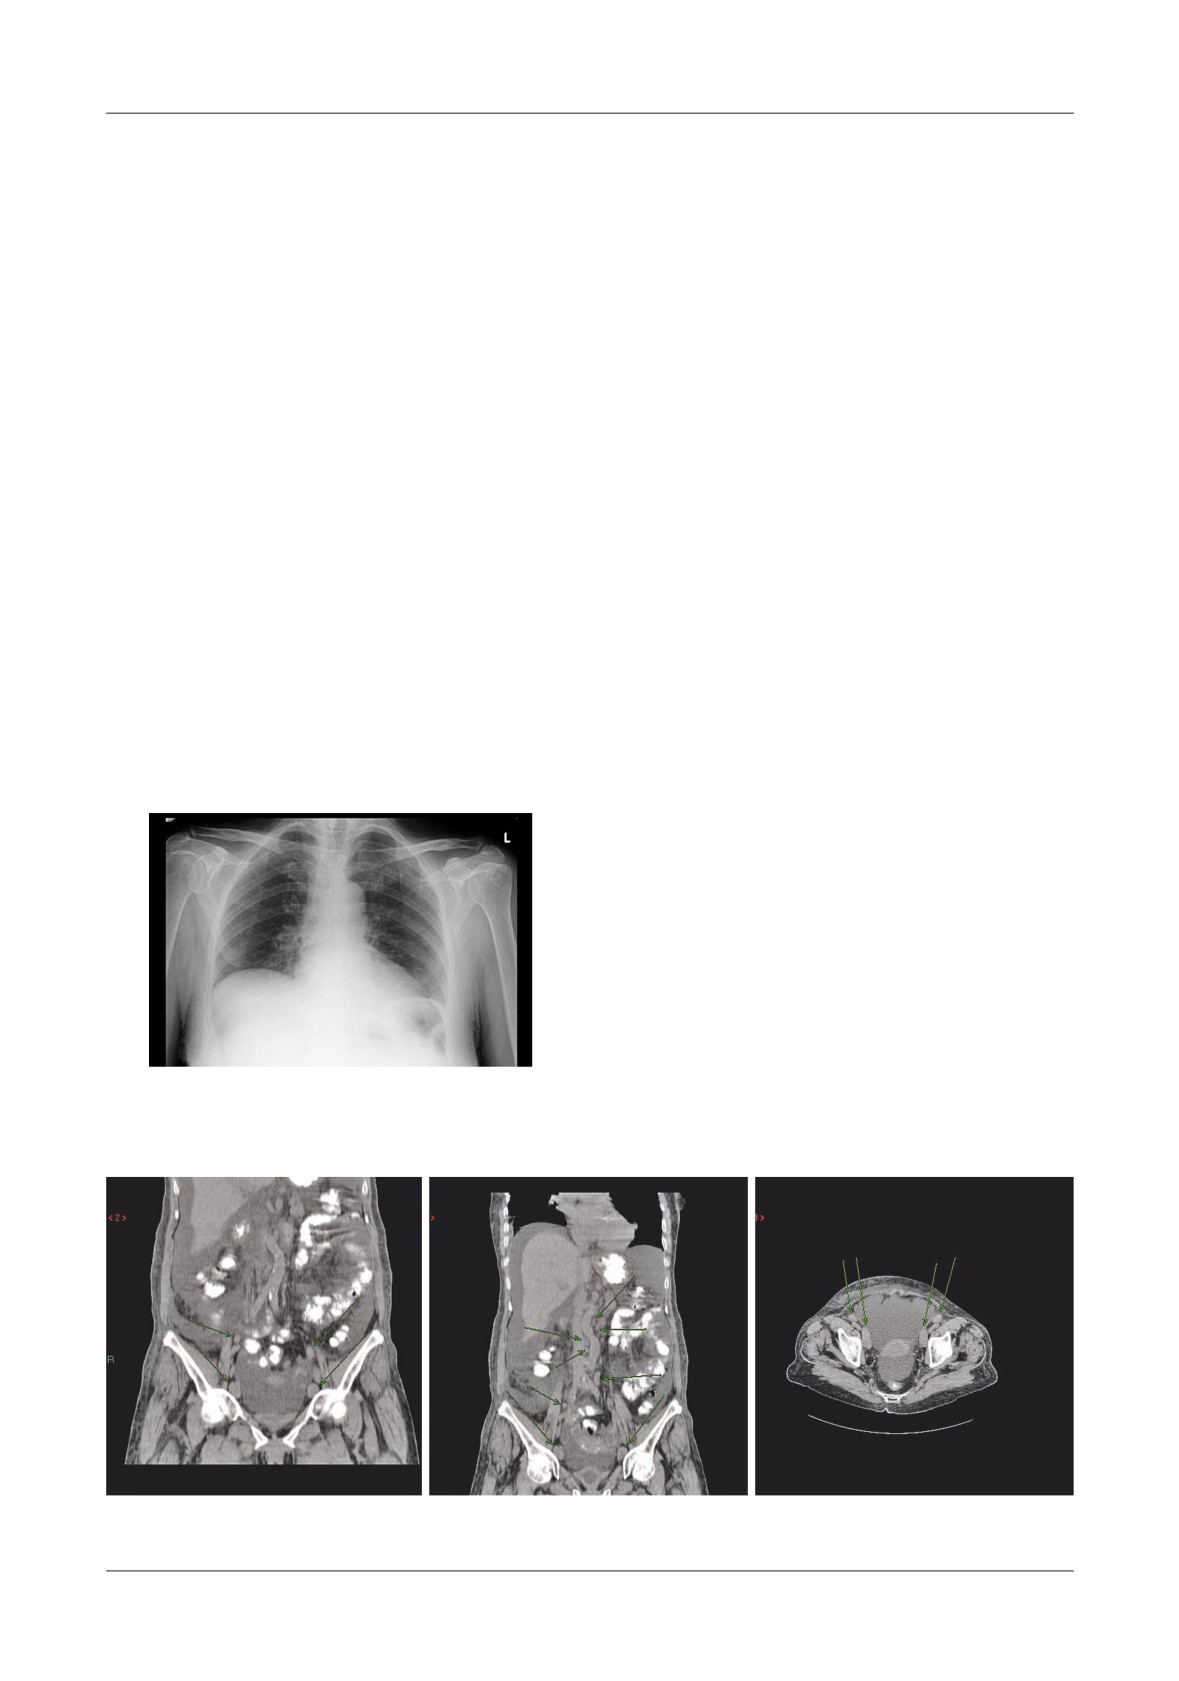

Figure 6. A - Normally enhancing pancreas with peripancreatic  uid collections (D=duodenum,

S=stomach, F= uid, P=pancreas), B - Transverse colon is air  lled and distended, C - Native

abdominal  lm showing distension of transverse colon

Figure 7. Intrasplenic and subcapsular

Figure 8. Splenomegaly and gastric varices with

hemorrhage (H=hemorrhage, S=spleen,

two episodes of pancreatitis. Massive enlarged

P=pancreas)

spleen, with peripheral infarct

In 16 cases the stomach, duodenum, transverse

experience, arterial venous lumen obstruction can lead

colon involved localized spasm at the splenic   exure of

to segmental colonic or proximal small bowel ischemia

the colon.    is explains the signi cant distension of the

and infarction (Figure 9).

proximal air- lled transverse colon (Figure 6)

Transitory small volume ascites was relatively a

In solid organ involvement, splenic involvement

frequent CT  nding, in 10 cases of the patients with AP.

was the most common because of the topography

e true pancreatic ascites can occur early, or after

between the pancreatic tail and splenic hilum (Figure 7,

several episodes of AP. In our study the patients with

8).

true ascites had increasing abdominal girth 24 cases,

abdominal pain 24 cases, weight loss

22 cases and

in19% of patients.    e diagnosis of infected pancreatic

occasional nausea or vomiting 2 cases.